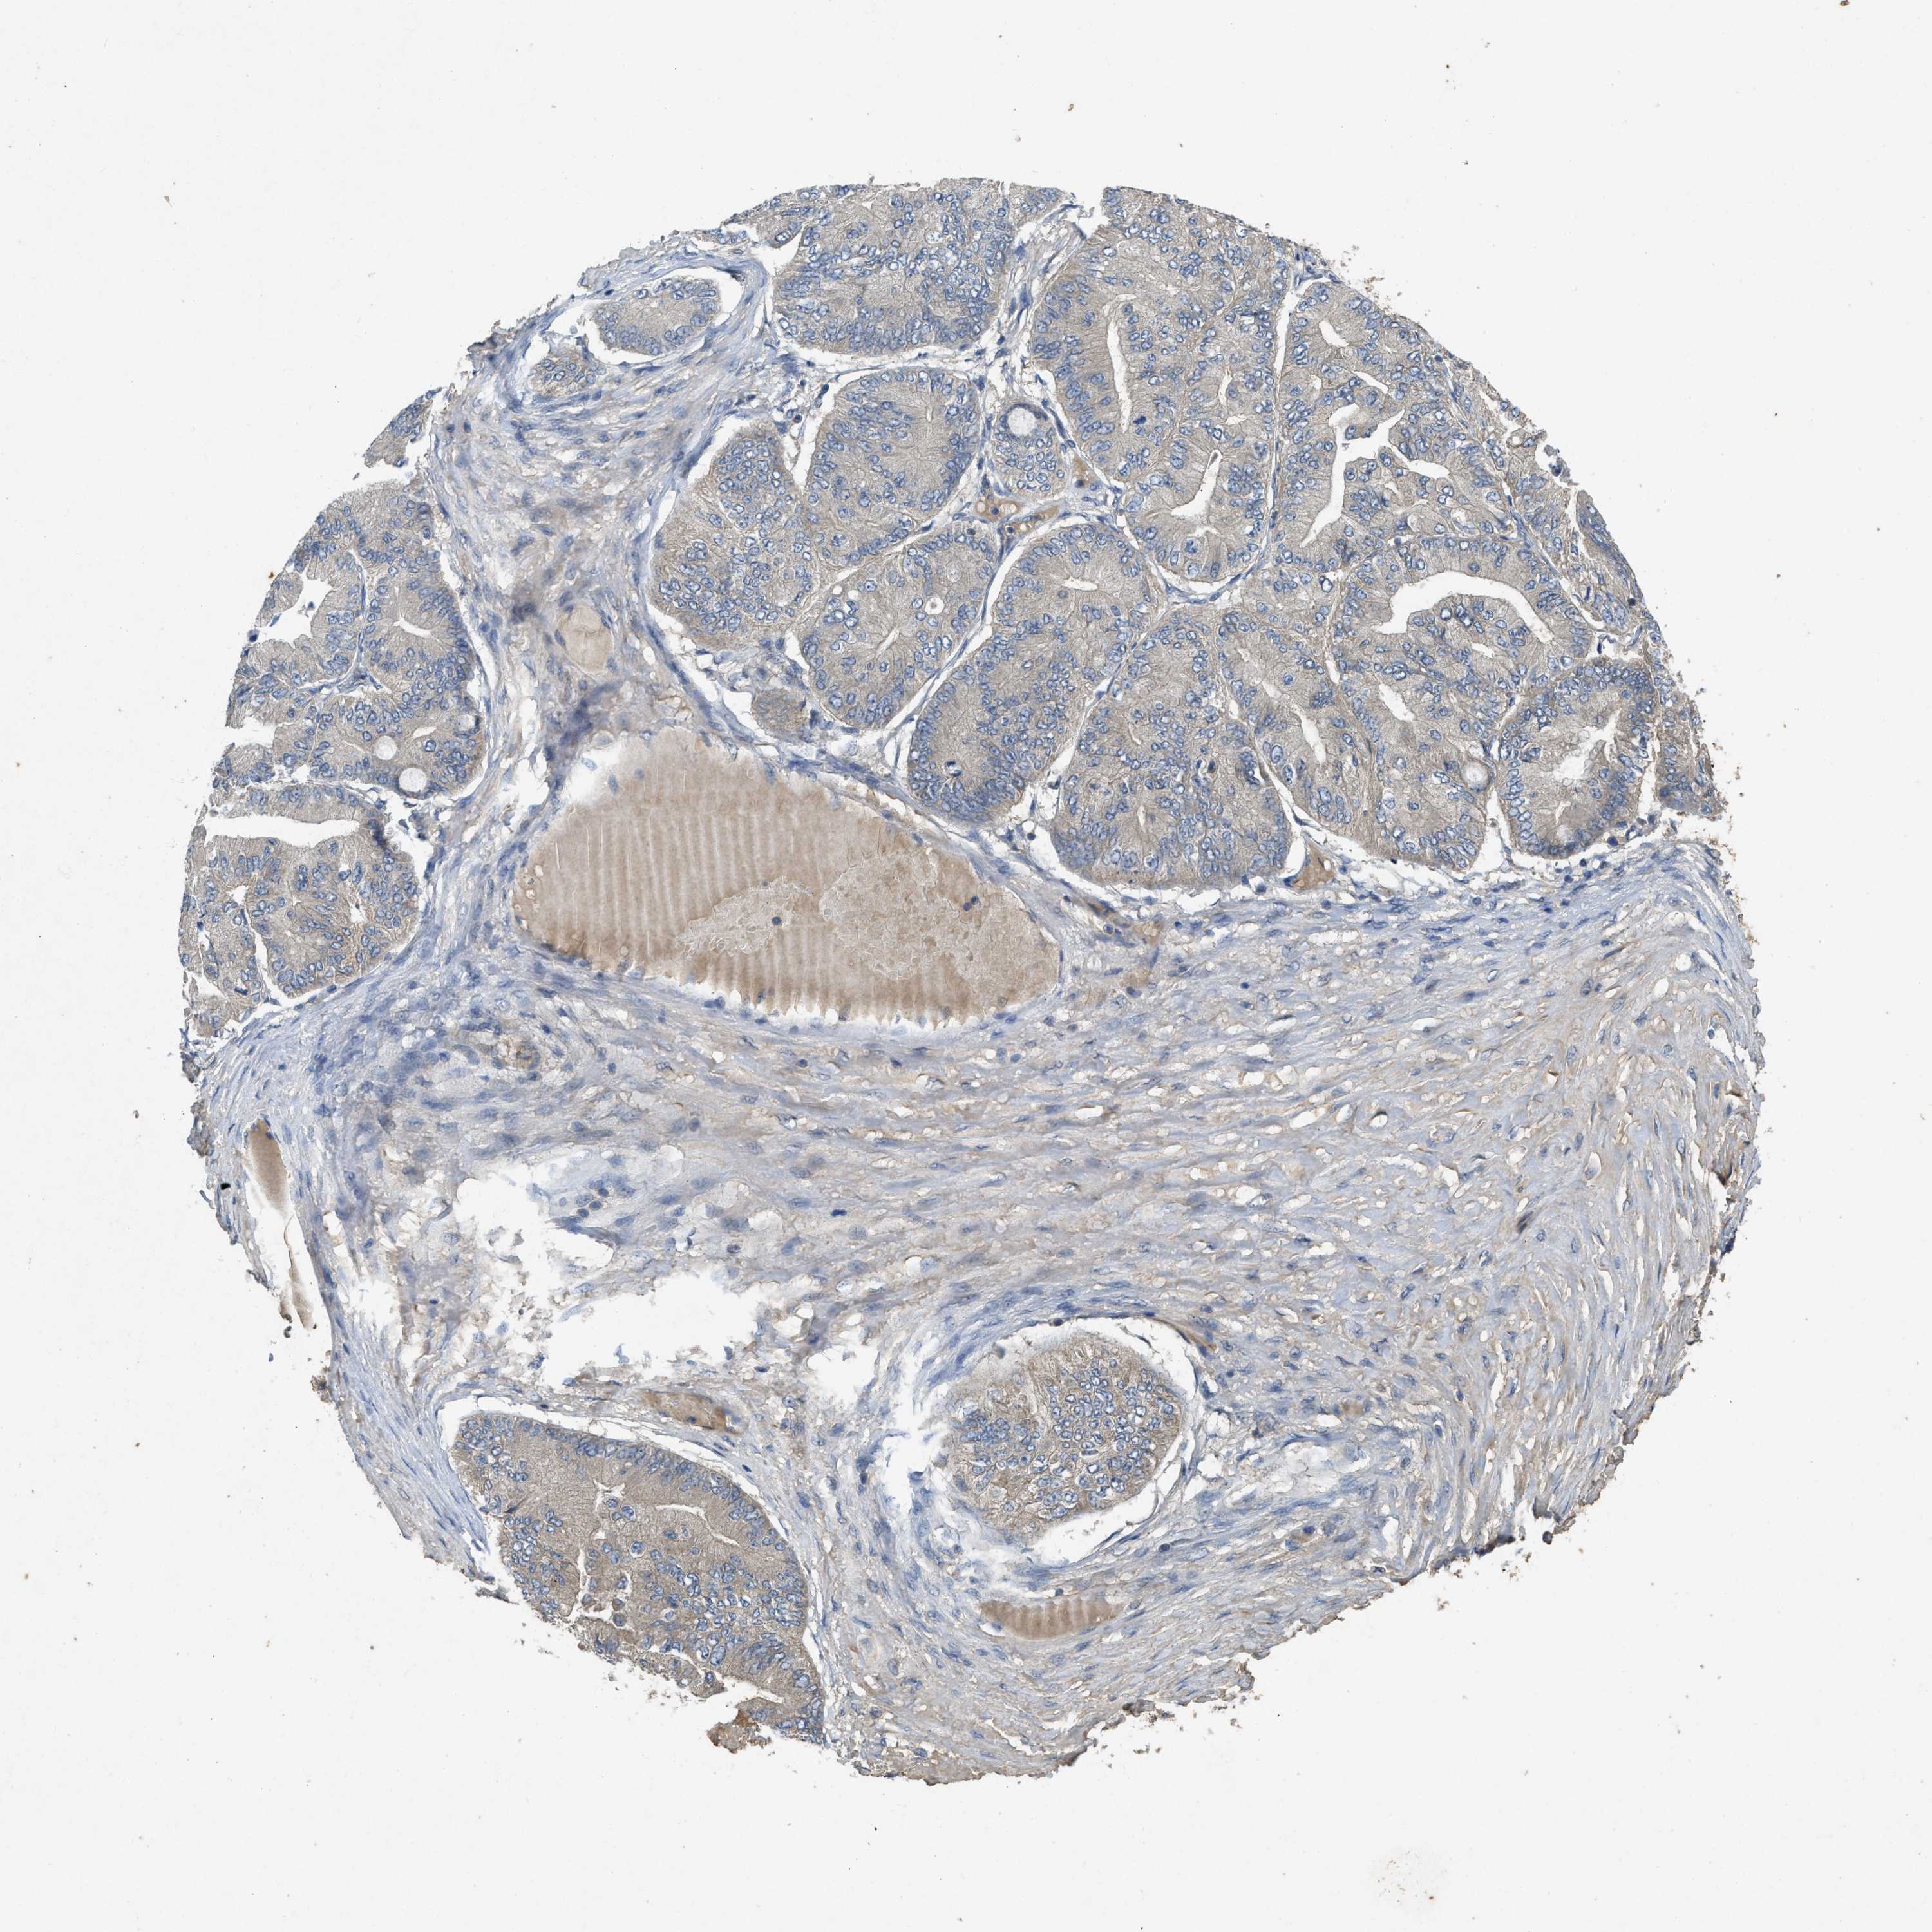

OVARIAN CANCER - Protein expressioni

A mouse-over function shows sample information and annotation data. Click on an image to view it in a full screen mode. Samples can be filtered based on level of antibody staining by selecting one or several of the following categories: high, medium, low and not detected. The assay and annotation is described here.

Note that samples used for immunohistochemistry by the Human Protein Atlas do not correspond to samples in the TCGA dataset.

Antibody stainingi

Antibody staining in the annotated cell types in the current human tissue is reported as not detected, low, medium, or high, based on conventional immunohistochemistry profiling in selected tissues. This score is based on the combination of the staining intensity and fraction of stained cells.

Each image is clickable and will lead to virtual microscopy that enables deeper exploration of all samples and also displays staining intensity scores, fraction scores and subcellular localization as well as patient and tissue information for each sample.

Antibody HPA012778

Antibody CAB018581

Cystadenocarcinoma, serous, NOS

Carcinoma, endometroid

Cystadenocarcinoma, mucinous, NOS

Carcinoma, NOS